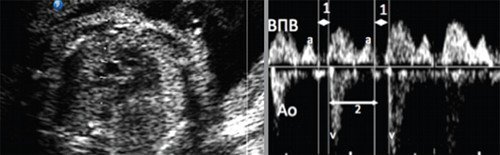

При предсердной бигеминии или тригеминии (преждевременных блокированных сокращениях предсердий) частота сокращений желудочков плода может снижаться до 60-100 уд/мин. При этом блокируется проведение к желудочкам каждого второго (бигеминия) либо каждого третьего (тригеминия) предсердного импульса (рис. 7-9).

а) Каждое третье сокращение предсердия (стрелка) возникает преждевременно и блокируется, не проводится к желудочку.

б) В результате формируется желудочковая брадисистолия 76 уд/мин.